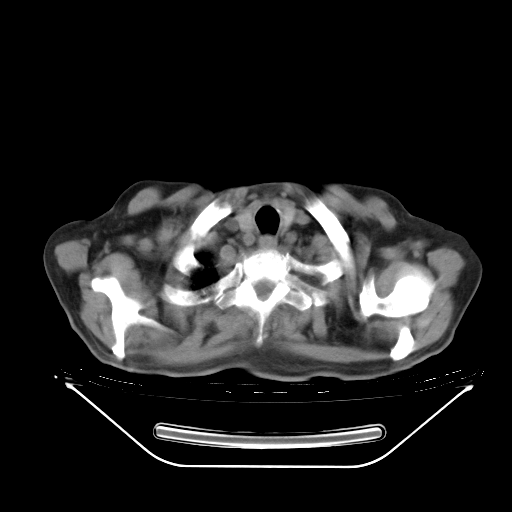

胸腹部CT,诊断意见:左上肺叶钙化灶、左侧胸膜局限性增厚并钙化、胆囊炎。描述部分肺组织呈磨玻璃样改变。